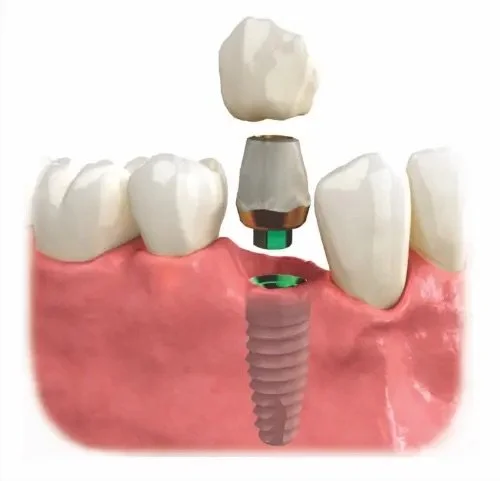

1. Dental Implant

Replaces the root and the crown

Preserves bone and surrounding teeth

Can last decades with proper care

Doesn’t rely on neighboring teeth for support

The implant acts as the “root” of your new tooth.

Most patients experience only mild soreness, usually less than having a tooth extracted.

In select cases, we can place a temporary tooth the same day for aesthetics.

Once healing is complete, we attach the custom abutment and crown.

The crown is designed to perfectly match the shape and color of your natural teeth.

Our high-quality ceramic materials are both durable and lifelike.

The result: a tooth that looks, feels, and functions just like your own.